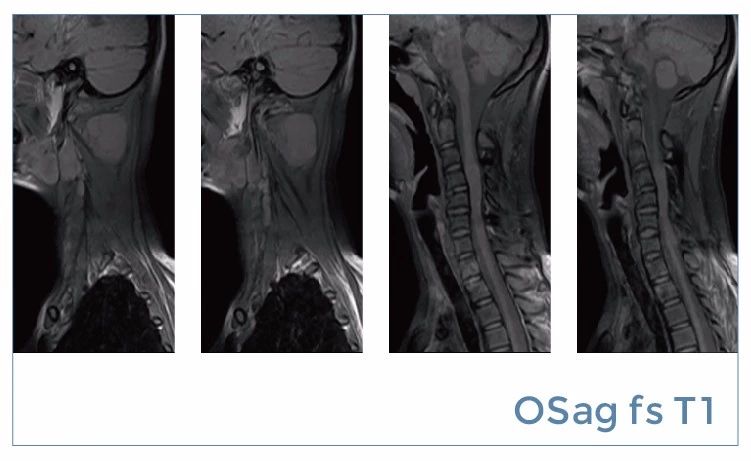

【朗润影像档案】磁共振影像病例分享(编号20190816)